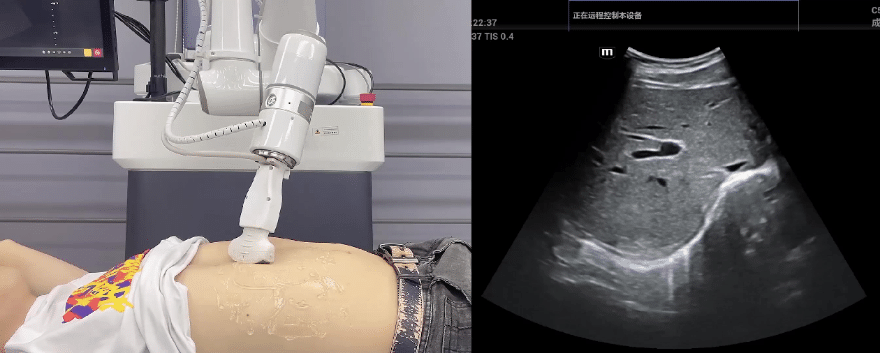

AG庄闲协作机器人搭载库柏特自主研发的机器人遥操作、多模态数据采集与处理、机器人模仿学习、机器人力位控制等技术升级变革传统超声,可实现远程+自主超声扫查与诊断,从传统远程超声仅能对话会诊变革升级为能对话、能操作,使得基层患者可就近享受异地三甲专家扫诊服务。实现专家端与患者端远程连接,并支持专家端与多路患者端自由切换控制。

AG庄闲协作机器人与超声深度打通,最大程度保留医生左右手同时操作传统超声的习惯,并改善其舒适性,超声检查实际应用场景展示如下:

肝脏、胆囊、胰腺扫查